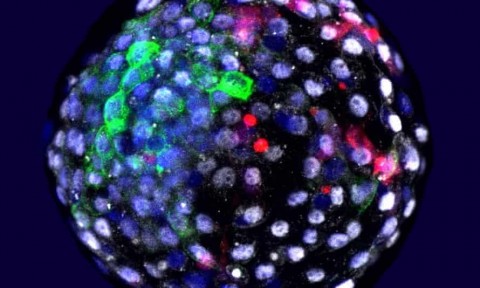

Uma foto emitida pelo Salk Institute mostra células humanas cultivadas em um embrião de macaco em estágio inicial. Fotografia: Weizhi Ji/Kunming Universidade de Ciência e Tecnologia/PA

Uma foto emitida pelo Salk Institute mostra células humanas cultivadas em um embrião de macaco em estágio inicial. Fotografia: Weizhi Ji/Kunming Universidade de Ciência e Tecnologia/PA

Embriões de macacos contendo células humanas foram produzidos em laboratório, um estudo confirmou, estimulando um novo debate sobre a ética de tais experiências. Os embriões são conhecidos como quimeras, organismos cujas células provêm de dois ou mais "indivíduos" e, neste caso, espécies diferentes: um macaco de cauda longa e um humano.

O estudo confirma os rumores publicados no jornal espanhol El País em 2019 de que uma equipe de pesquisadores liderada por Belmonte tinha produzido quimeras macaco-humanas. A palavra quimera vem de uma besta na mitologia grega que se dizia ser parte leão, parte cabra e parte cobra. O estudo, publicado na revista Cell, revela como os cientistas pegaram células fetais humanas específicas chamadas fibroblastos e as reprogramaram para se tornarem células-tronco. Estas foram então introduzidas em 132 embriões de macacos de cauda longa, seis dias após a fertilização.

"Vinte e cinco células humanas foram injetadas e em média observamos cerca de 4% de células humanas no epiblasto do macaco", disse o Dr. Jun Wu, um co-autor da pesquisa agora na Universidade do Texas Southwestern Medical Center. Os embriões puderam se desenvolver em placas de petri e foram terminados 19 dias após as células-tronco terem sido injetadas. A fim de verificar se os embriões continham células humanas, a equipe projetou as células-tronco humanas para produzir uma proteína fluorescente.

Entre outras descobertas, os resultados revelam que todos os 132 embriões continham células humanas no sétimo dia após a fertilização, embora à medida que se desenvolviam, a proporção contendo células humanas caiu com o tempo.

"Demonstramos que as células-tronco humanas sobreviveram e geraram células adicionais, como aconteceria normalmente quando os embriões de primatas se desenvolvem e formam as camadas de células que eventualmente levam a todos os órgãos de um animal", disse Belmonte. A equipe também relatou que eles encontraram algumas diferenças nas interações células-células entre células humanas e células de macacos dentro de embriões quiméricos, em comparação com os embriões dos macacos sem células humanas.